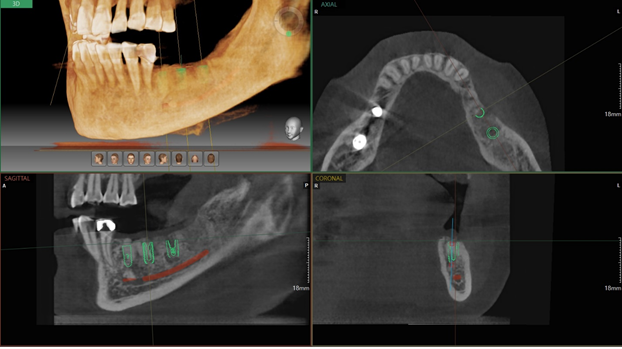

위에 사진과 같이 저희는 3D 구강 스캐너를

통해 임플란트 치료에 있어 컴퓨터

분석을 이용하고 있습니다.

임플란트를 담당하는 의료진 모두

풍부한 임상 경험을 갖고 있지만

컴퓨터로 분석하여 명확한 위치에

임플란트가 식립 될 수 있도록 위치를

잡아주기 때문에 실수가 없습니다.

치아는 신경이 많이 위치하기에

예민하며 적은 오차도 추후에는

큰 차이가 날 수 있기 때문에

컴퓨터 분석과 모의 수술을 통해

몇 차례 확인한 후 진행합니다.

이는 CT 모의 술식으로 사전에 뼈와 기타

구조물을 분석하기 위해 진행합니다.

임플란트 모든 치료의 과정을 디지털

데이터로 사용하여 진행하며 이로 인해

치료 후 붓기나 통증, 출혈의 경감에

도움이 되어 회복이 빠릅니다.

1:1 맞춤 임플란트를 3D 모의 수술을

통해 개인의 구강 구조와 잇몸뼈에

꼭 맞도록 식립하는 위치, 각도,

깊이 등을 전반적으로 파악하여

진행하기 때문에 처음 치과에

오실 때부터 치료를 완료하고

나가실 때까지 온전하고 명확한

치료를 받으실 수 있도록 하고 있습니다.